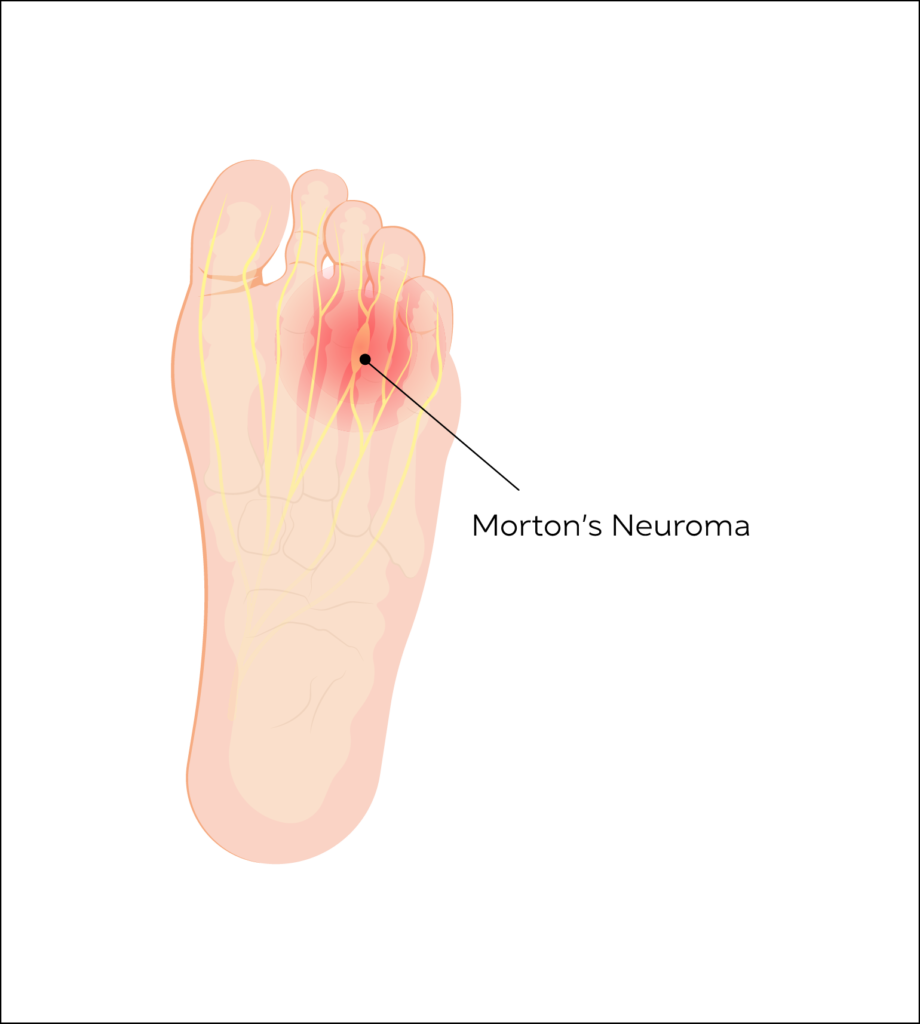

Morton’s Neuroma

Morton’s Neuroma is when a small digital nerve normally found between the bones of the forefoot gets inflamed and produces forefoot pain. Mostly seen between the 3rd and 4th toes.

This condition is seen predominantly in the female population and can affect up to 20% of the population in general.

Morton’s neuroma can present as sharp shooting pain in the forefoot with activities including weight bearing. Some patients report symptoms of walking on “pebbles”.

Ultrasound can be used to not only diagnose the condition, but also target steroid injections into the lesion and help relieve pain.